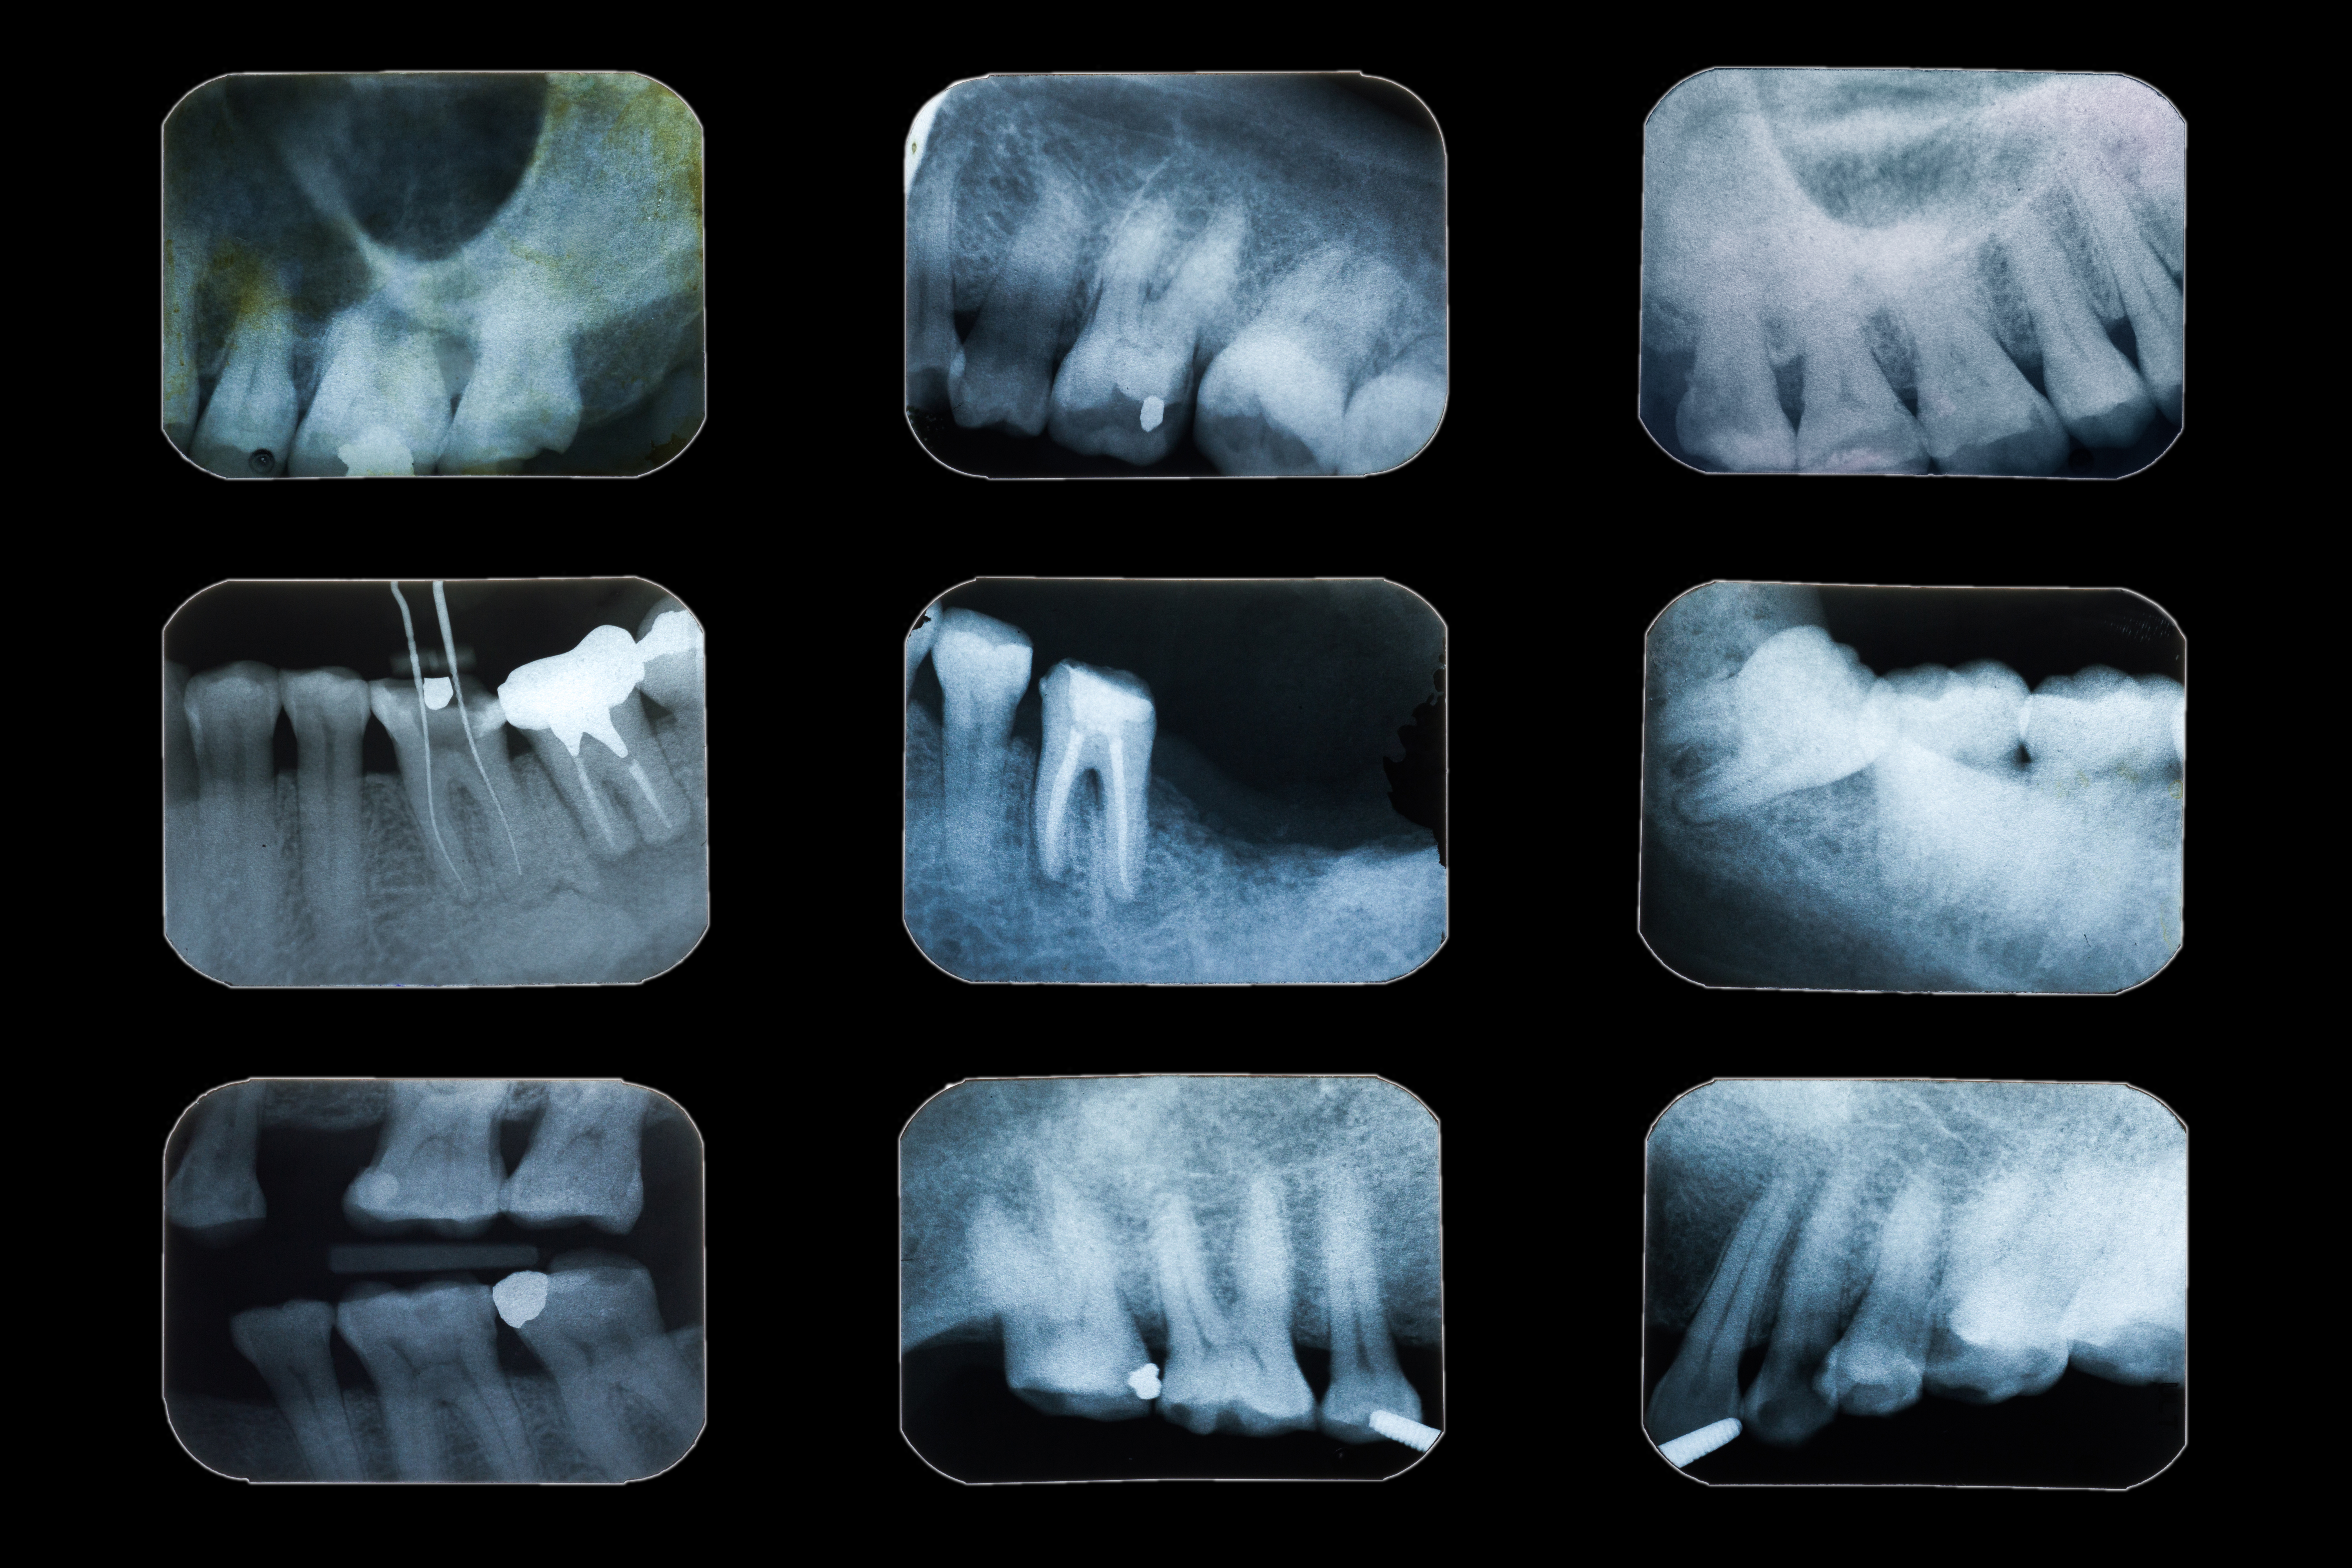

X-ray diagnostics of dental condition

Dental x-ray diagnosis is the gold standard in dental examination and has been effectively used for decades. This widely used…

Targeted dental x-ray

A single-tooth x-ray is a simple, quick, and affordable diagnostic method frequently used in dental diagnostics to assess oral health.…

Dental Visiography

To obtain a detailed image of a tooth, we use a digital X-ray device known as a visiograph. This advanced…

• Dental point X-ray examination

50 PLN

Modern diagnostic technology dentistry provides enhanced image clarity, lower radiation, and faster results. At our dental diagnostic center, we use digital x-ray dental, CBCT scans, and intraoral cameras for accurate, non-invasive diagnostic evaluation in dentistry.

• Is dental diagnostic imaging safe for patients?

Yes. Our advanced dental diagnostics are performed using certified, low-radiation digital diagnostic equipment in dentistry. All procedures follow international safety standards and are suitable for adults and children alike.